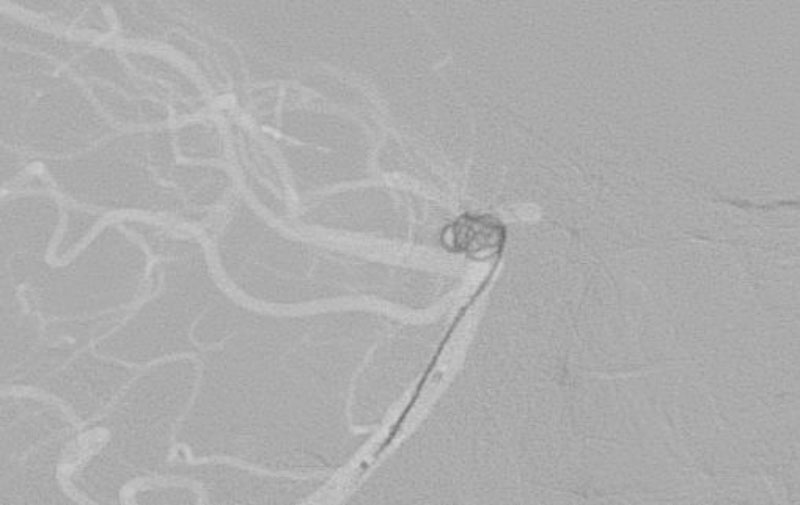

No.1631 手術前

No.1631 手術中

No.1631 手術後